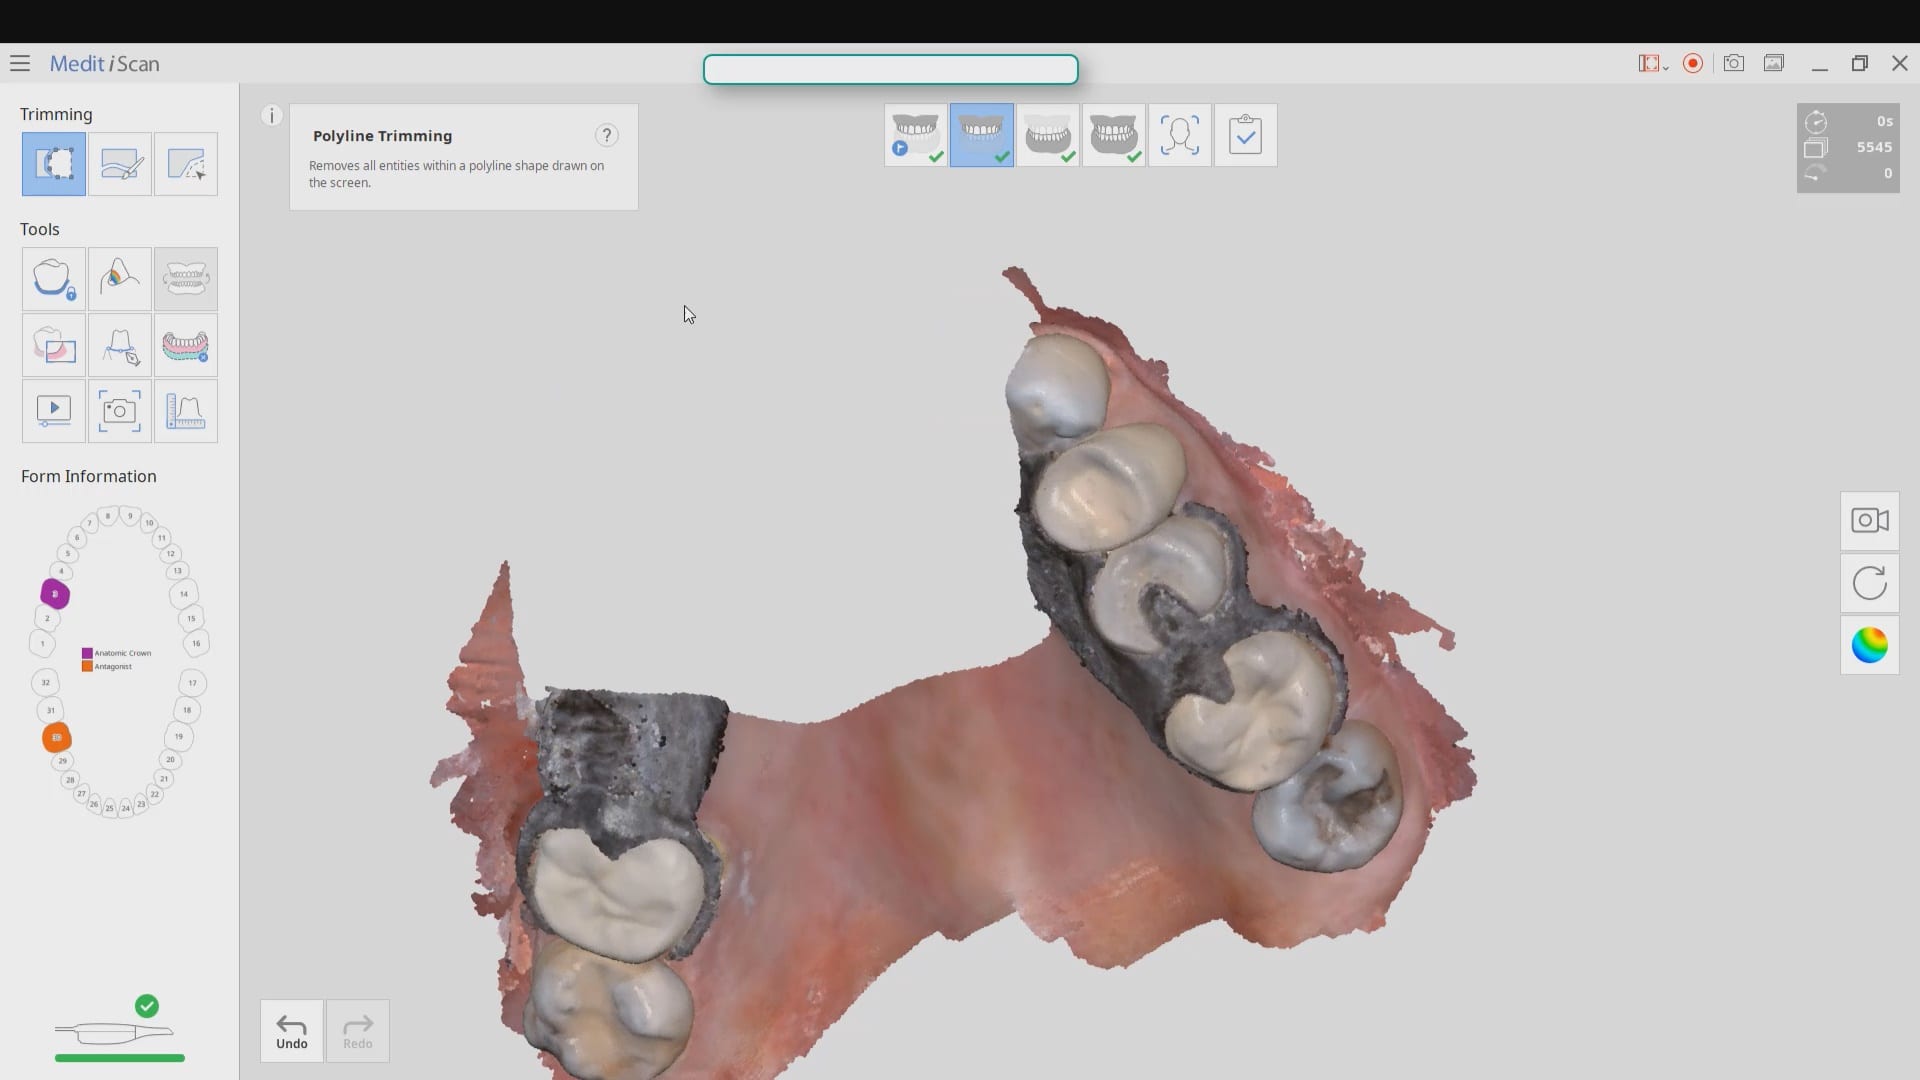

Full Arch Scan by The Shining 3D Aoralscan

March 16, 2020In this video we demonstrate how the Aoralscan can complete a full arch scan utilizing the basic principles of digital impressioning. Proper retraction, isolation, and scanning technique lead to high […]